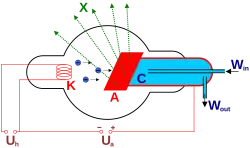

Schematische Darstellung einer Röntgenröhre

Schematische Darstellung einer Röntgenröhre